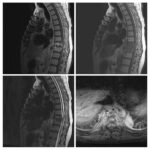

Neurosurgery and neuroradiology always go hand in hand. This little weekly activity is going to enhance the scan reading skills of our audience in an interactive way. Waiting for the answer for a week will keep the curiosity alive and will keep our target audience hooked to the website. It will prove to be a seamless share of knowledge and reading skills.

Dr. Saqib Kamran Bakhshi started the PANS Weekly Image Challenge in 2022, and his creativity and efforts made it a popular activity; engaging trainees and consultants in Pakistan and abroad.